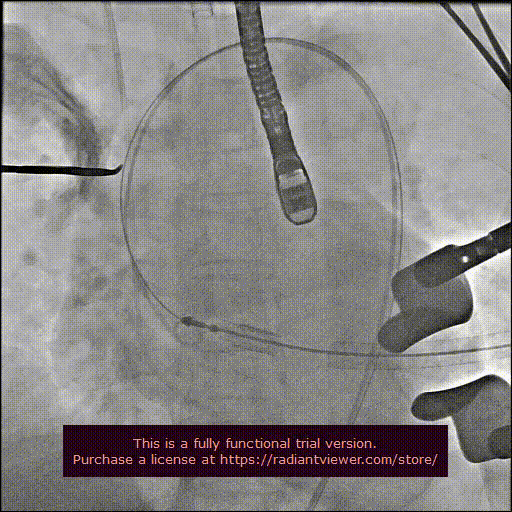

用经胸超声心动图确定心尖位置,并做好标记。常规肝素化,按照心尖标记,行第5、6 肋间左胸前外侧小切口,充分暴露心尖后将心包切开并悬吊,用3-0 Prolene 线加毛毡片完成荷包缝合。经股动脉植入6Fr鞘管,并插入猪尾造影导管至主动脉根部,造影确定主动脉瓣瓣环水平及两侧冠状动脉开口。

经心尖途径置入 J-Valve 瓣膜输送系统,在升主动脉部打开定位件,调整角度,轻轻向后牵拉输送器使定位件进入主动脉窦内。联合主动脉根部造影和食管超声观看定位件是否定位于窦底,形态随着心脏跳动而自然摆动即可。下降瓣膜至主动脉瓣环内,在主动脉瓣口释放瓣膜支架,此过程无需快速起搏。瓣膜成功释放后移除瓣膜输送系统。行主动脉根部造影及经食管超声检查,对瓣膜功能、位置情况进行术后即刻评估。确认位置良好、功能正常后,移除导丝及输送系统,并收紧心尖荷包缝线打结固定。

造影显示主动脉窦部

从心尖置入输送系统

定位件入窦

瓣膜降至瓣环平面

释放瓣膜

造影确认瓣膜位置

撤出输送系统

造影确认植入效果